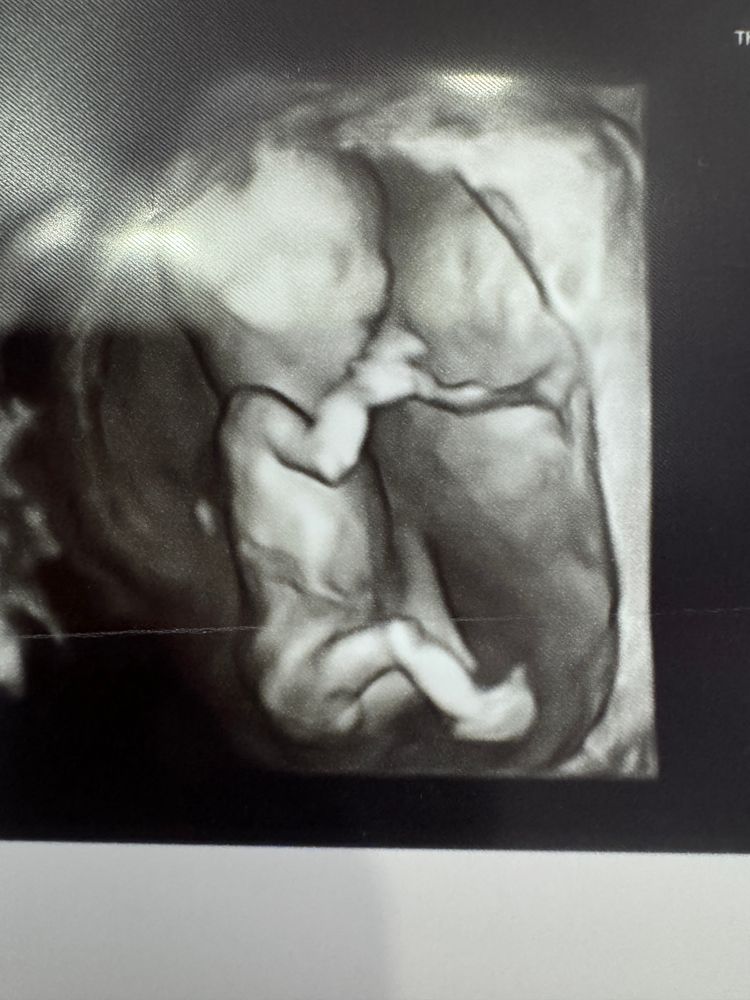

Пол по половому бугорку

Девочки, помогите пожалуйста❤️🙏 13 недель, сходила на узи. Видно тут половой бугорок и возможно предположить пол малыша?! Дурная беременная голова не дает мне покоя😂

Ой женщины, вы такие женщины!😂 мадам сидит там и ногу на ногу сделала 😂 еще и пальцы во рту- деловая☺️ (3d)

Там кстати половые губки видно очень

Мне кажется девочка, а 3д бугорок моей малявки оооочень похож на ваш, как бы вниз направлен)